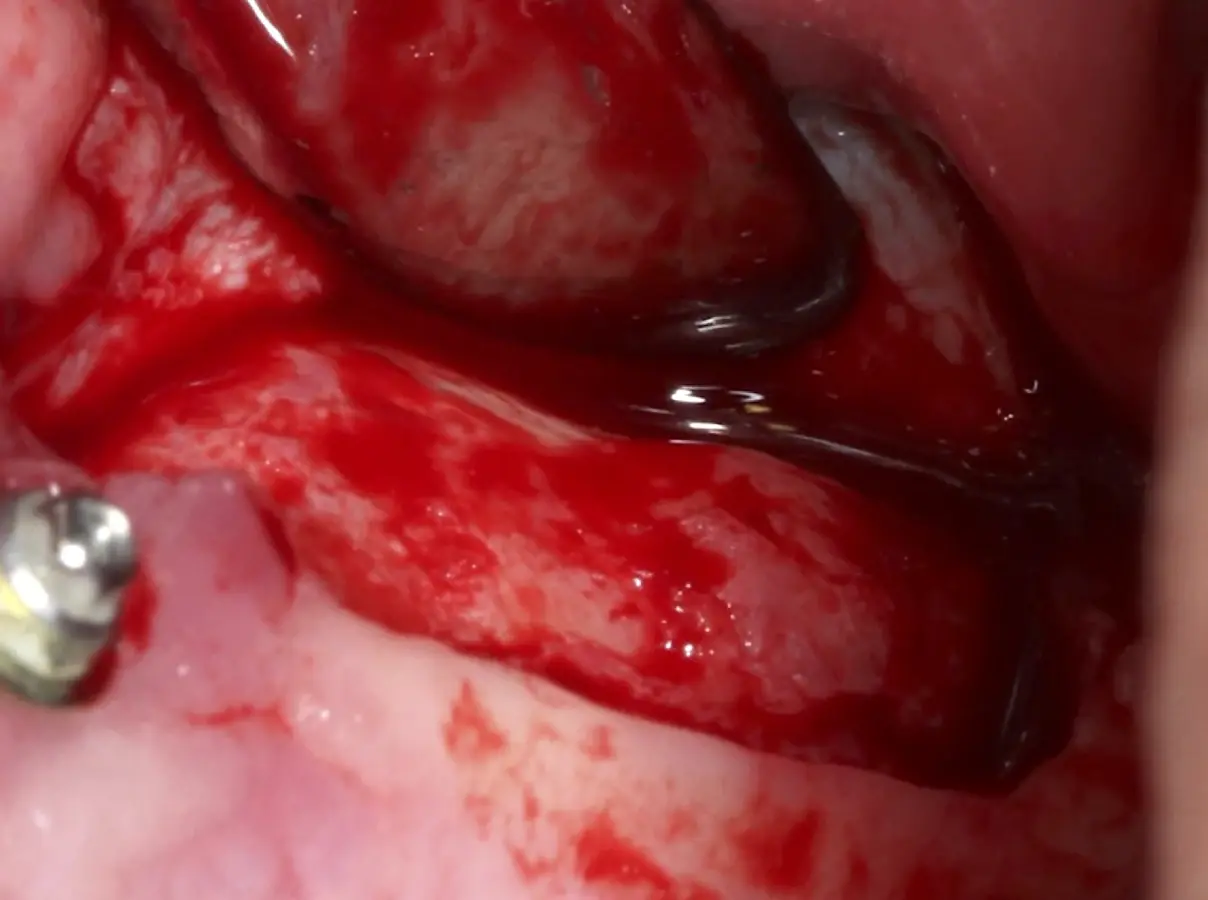

Una vez elevado el piso sinusal según la planificación se realiza la evaluación clínica de la integridad de la membrana y de posibles desgarros a través de la maniobra de Valsalva.24 Consiste en pedir al paciente que respire profundamente y retenga el aire, cerrar la boca, apretar la nariz con los dedos y forzar la salida de aire. Al final de la prueba, es necesario mantener la presión entre 10 a 15 segundos. Se identificará la movilidad de la membrana y la ausencia de burbujas de aire para corroborar que no hay perforaciones. Dependiendo de la decisión clínica se puede optar por adicionar en la superficie de la membrana de Schneider membranas de colágeno o de plasma rico en fibrina (PRF) para dar mayor soporte durante la inserción del biomaterial de relleno óseo (Figura 10).

Figura 10. Membrana de PRF introducida dentro del seno maxilar.